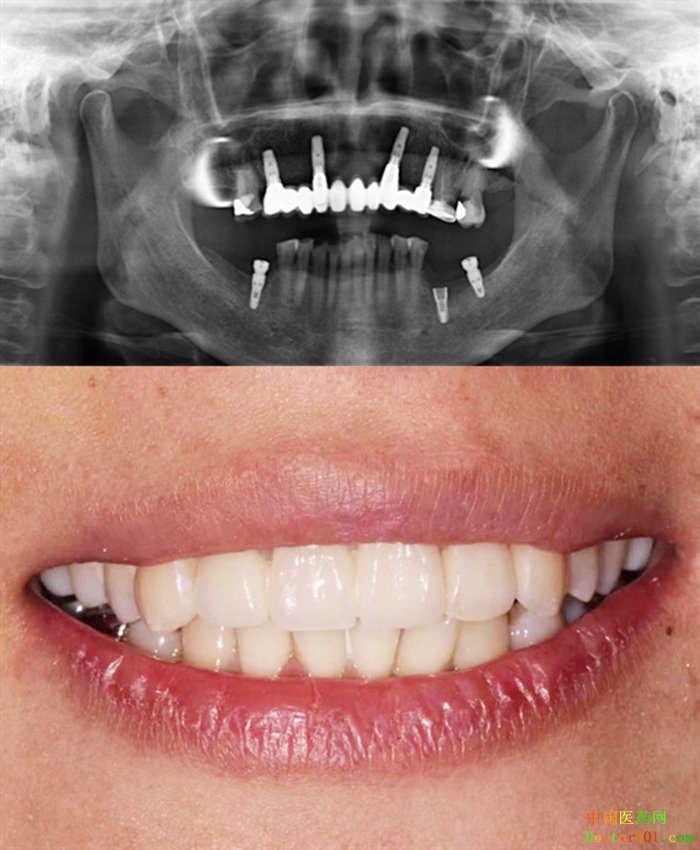

郭晓强院长作为天津市中诺口腔医院院长,高龄、高难度种植专家,擅长单颗多颗、半口全口种植、“立得用”种植牙体系、即刻种植、即刻负重、微创种植、前牙美学种植、all-on-4种植技术,对各类牙槽骨骨量不足、牙龈萎缩等疑难种植病例有丰富的临床经验。

同时郭晓强院长还主攻老龄种植牙技术,在他的治疗下,很多的缺牙老人都重新拥有了一口属于自己的好牙,就连全口牙缺失的老人完成修复后恢复了正常吃饭。郭晓强院长能将条件差的牙槽骨重新“激活”,4颗种植体即可完成半口种植;大大缩短种植时间,让老人不用往返折腾。